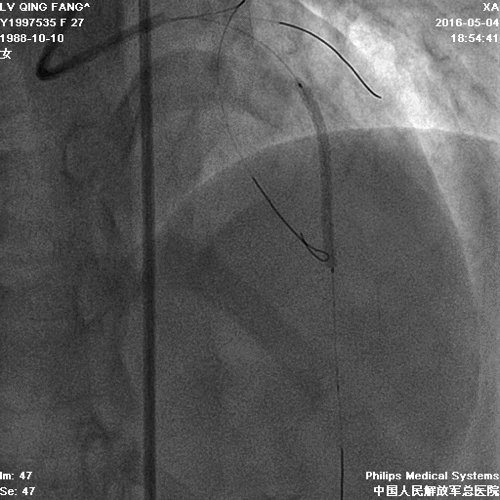

PCI